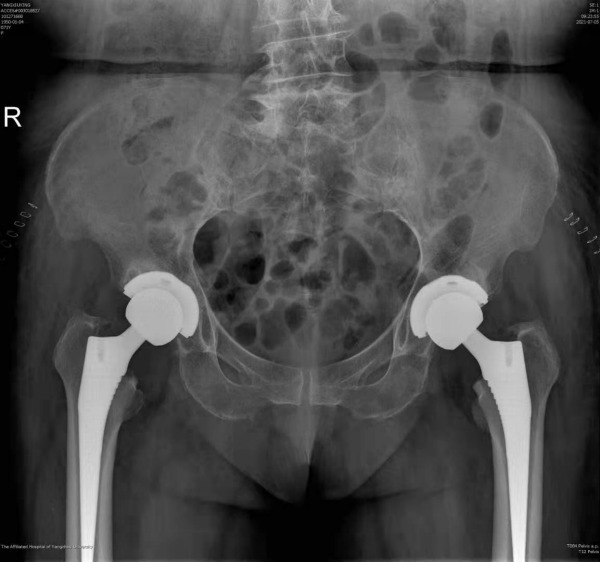

7月2日,我院骨科关节重建组徐松诊疗团队顺利为一名双侧髋关节骨性关节炎患者实施了双侧人工全髋关节置换手术。该手术为我院首次同期为双侧股骨头坏死患者进行人工全髋关节置换手术,突破了需要分两次进行全髋关节置换的治疗传统,缩短了该类疾病的治疗周期,减轻了该类患者的经济负担,标志着我院骨科关节重建技术水平迈上新的台阶。

杨女士今年71岁,长年遭受双侧髋部疼痛的困扰,基本丧失行走能力和劳动能力,生活质量受到严重影响。近日,她慕名来到我院骨科就诊,骨科副主任医师徐饶仔细读片后判断杨女士双侧髋关节疼痛的主要原因是双侧髋臼发育不良继发双侧股骨头坏死所致。目前杨女士的双侧股骨头已经磨损变形,关节间隙消失且疼痛明显,已经具备了进行双侧全髋关节置换的指征。